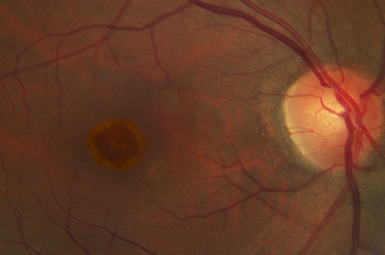

Macular Pucker

Numerous underlying conditions lead to scar tissue on the macula. When this affects vision, the scarring can be surgically removed.